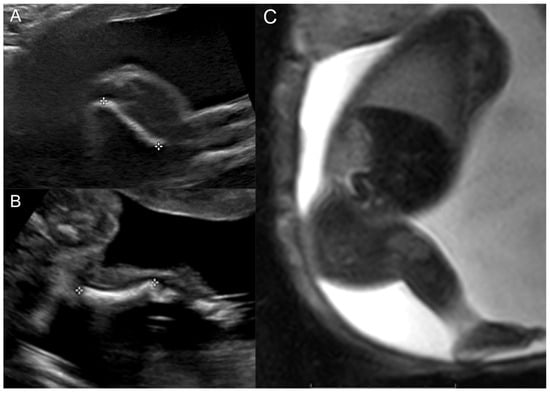

2.1. Case 1

2.2. Case 2

2.3. Case 3